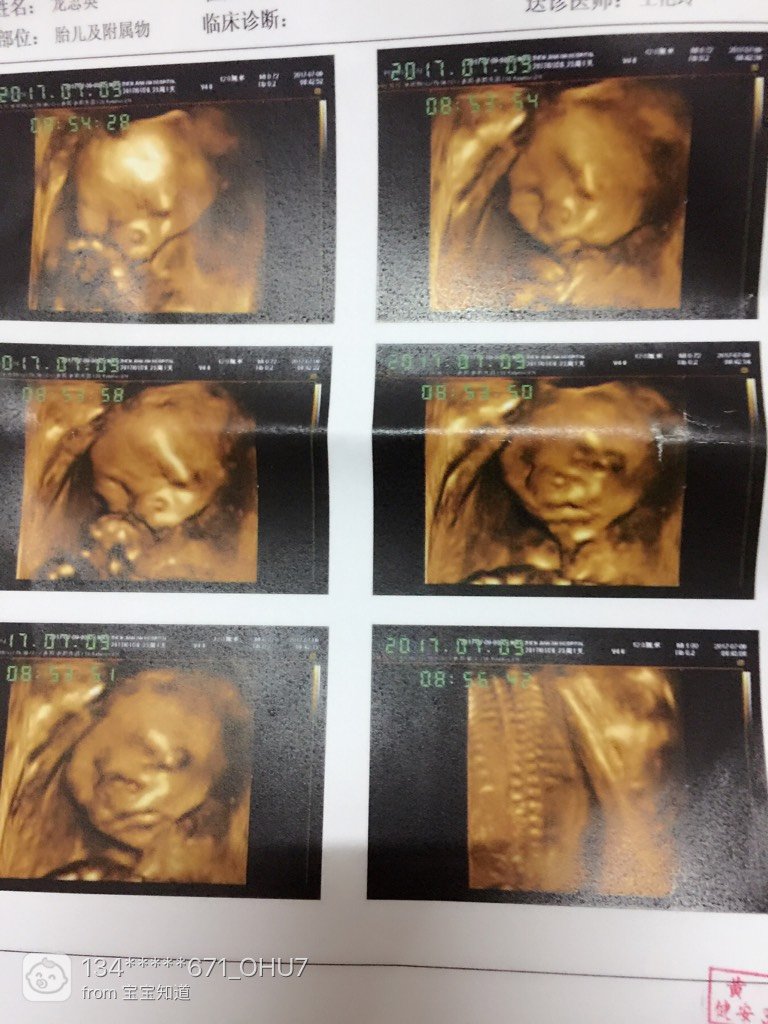

2个宝宝 LV.4我做四维的时候、我问医生也不说、但是我宝宝很配合,她说我们就宝宝很体谅我、我就说感觉好贴心、医生说对贴心贴心、我也不知道是什么意思、我再想是不是说我肚子里是女宝宝、那我就开心了,那样我就儿女双全了,好开心的[哈哈]

宝宝8岁1个月23天 LV.7小棉袄贴心吖[笑眼]我家宝宝不配合,我看了好多宝妈说吃甜的有用我就买了士力架[狂汗]吃之前做了半个小时左右医生让我去爬楼梯主要是宝宝挡脸了[狂汗]爬完楼梯回来我就吃士力架[喷]还是边吃边照宝宝都没点反应不带动一下的[不高兴]完事医生说起来再去爬楼梯[喷]这可折腾死我了